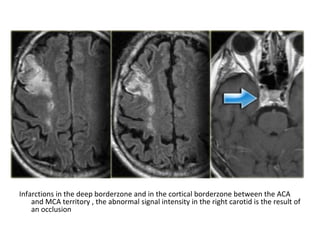

Infarctions in the deep borderzone and in the cortical borderzone between the ACA

and MCA territory , the abnormal signal intensity in the right carotid is the result of

an occlusion